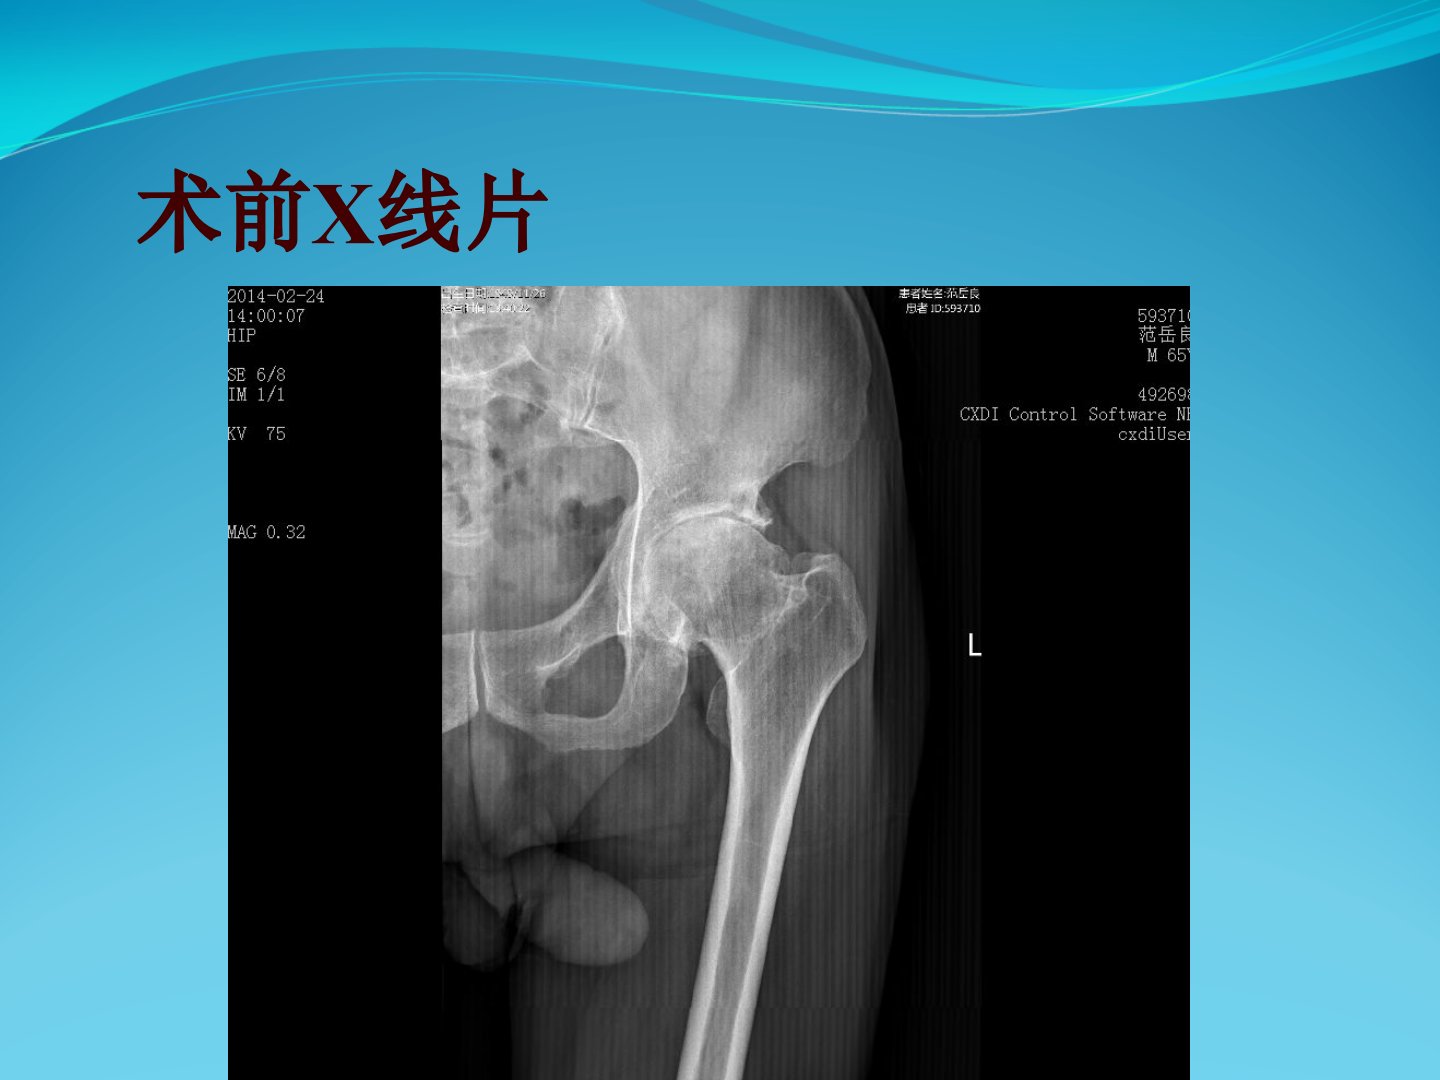

患者为65岁男性因“左髋疼痛15年加重伴活动受限1年余”入院。查体显示左髋存在压痛左侧“4”字征呈阳性左髋活动明显受限尤其以外展受限显著屈曲约135度后伸约25度外展仅10度内收及内外旋功能尚可。患者足背感觉运动正常股四头肌及胫前肌肌力为5级病理征阴性生理反射存在。患者进行了详细的术前检查包括X线片、CT片及三维CT片并进行了术前步态评估及术前准备。手术过程顺利术后复查X线片及CT片显示臼杯前倾和股骨侧前倾均良好并进行了术后步态评估。生产计划部内容与本病例无关。